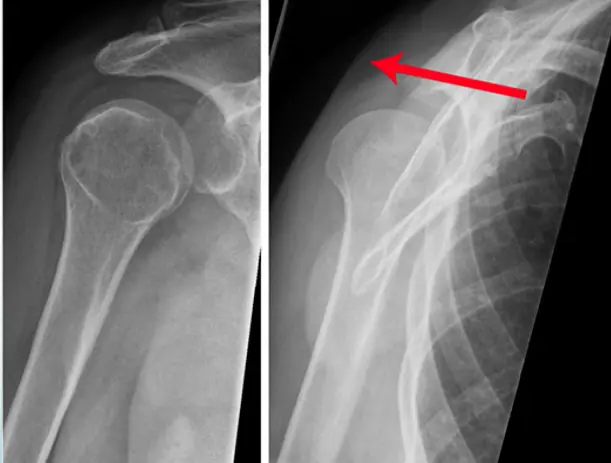

x-ray AP view of Shoulder Joint

- The image contains two X-ray views of a shoulder joint.

- The right X-ray is annotated with labels for various anatomical features.

- acromion

- clavicle

- coracoid process

- humeral head

- glenoid fossa

- greater tuberosity

- scapula

Patient: 17âyearâold male â fell from a bicycle, landing on his left shoulder.

Symptoms: Pain on shoulder movement; tender point medial to the shoulder; no skin lesions.

Imaging (Xâray, left side)

- Location: Middle third of the left clavicle

- Fracture type: Simple

- Fracture line: Transverse

- Displacement: Downward tilt of ââŻ35°

Special considerations: The fracture could be managed conservatively.

- Site: Greater tuberosity of the right humerus

- Type: Simple

- Fracture line: Vertical

- Displacements: None

- Special issues: Can be treated conservatively

Patient: 65âyearâold woman â slipped on a wet floor and fell onto her left shoulder.

Findings

- Site: upper humeral neck

- Type: comminuted fracture

- Fracture line: multiple (3âpart)

- Displacement: minimal

- Special issues: treated conservatively